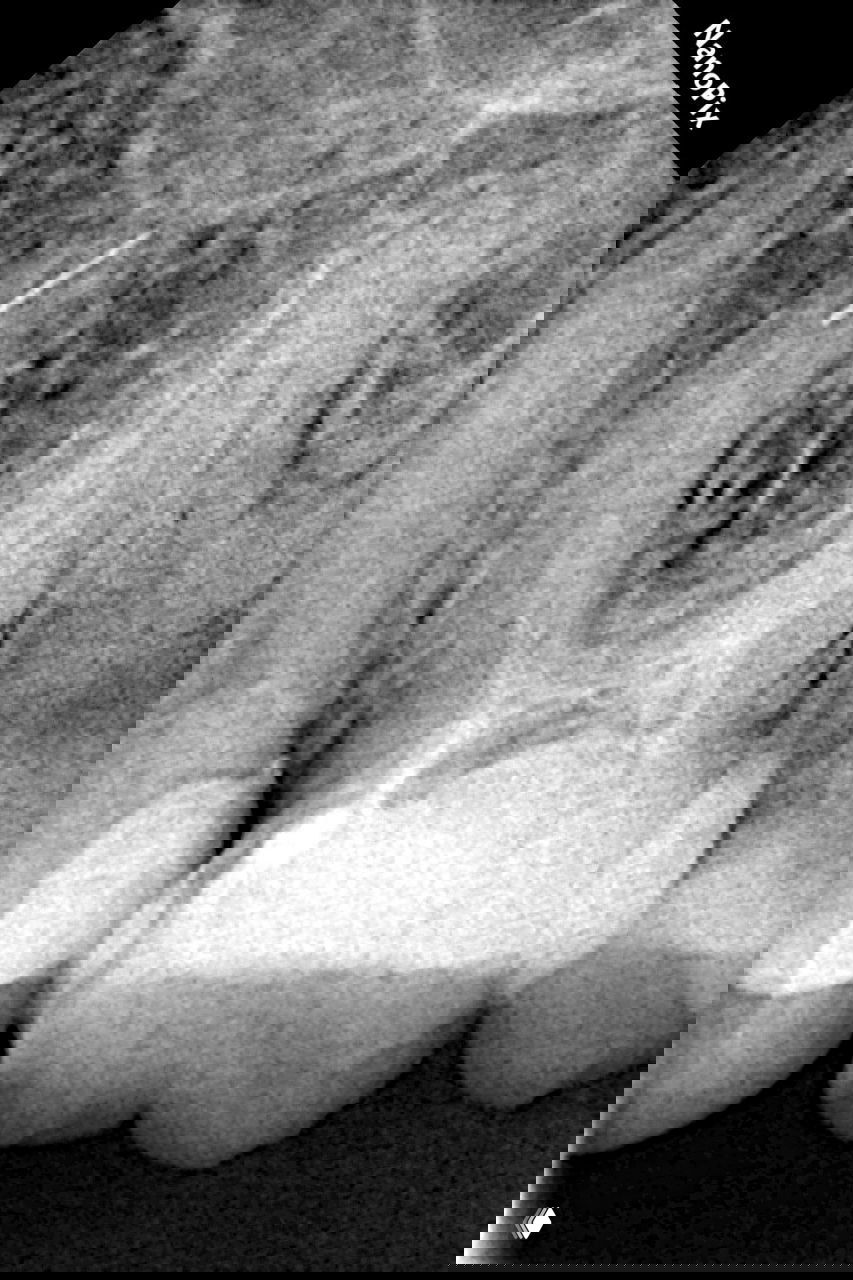

Поиск истинного хода МВ1 при слиянии с МВ2

Короткий клинический лайфхак: при ступени в МВ1 и слиянии МВ1 с МВ2 по КТ ищите истинный ход у стенки, смежной с МВ2.